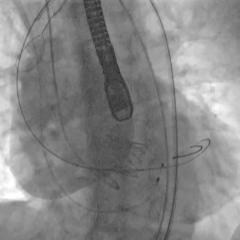

脱钩后造影,瓣膜无位移,可见瓣周漏

20mm球囊后扩,瓣膜形态改善

后扩后评估,可见少量瓣周漏

最终瓣膜位置稳定

TEE长轴:瓣膜深度可

TEE短轴:瓣膜展开良好,仅少量瓣周漏